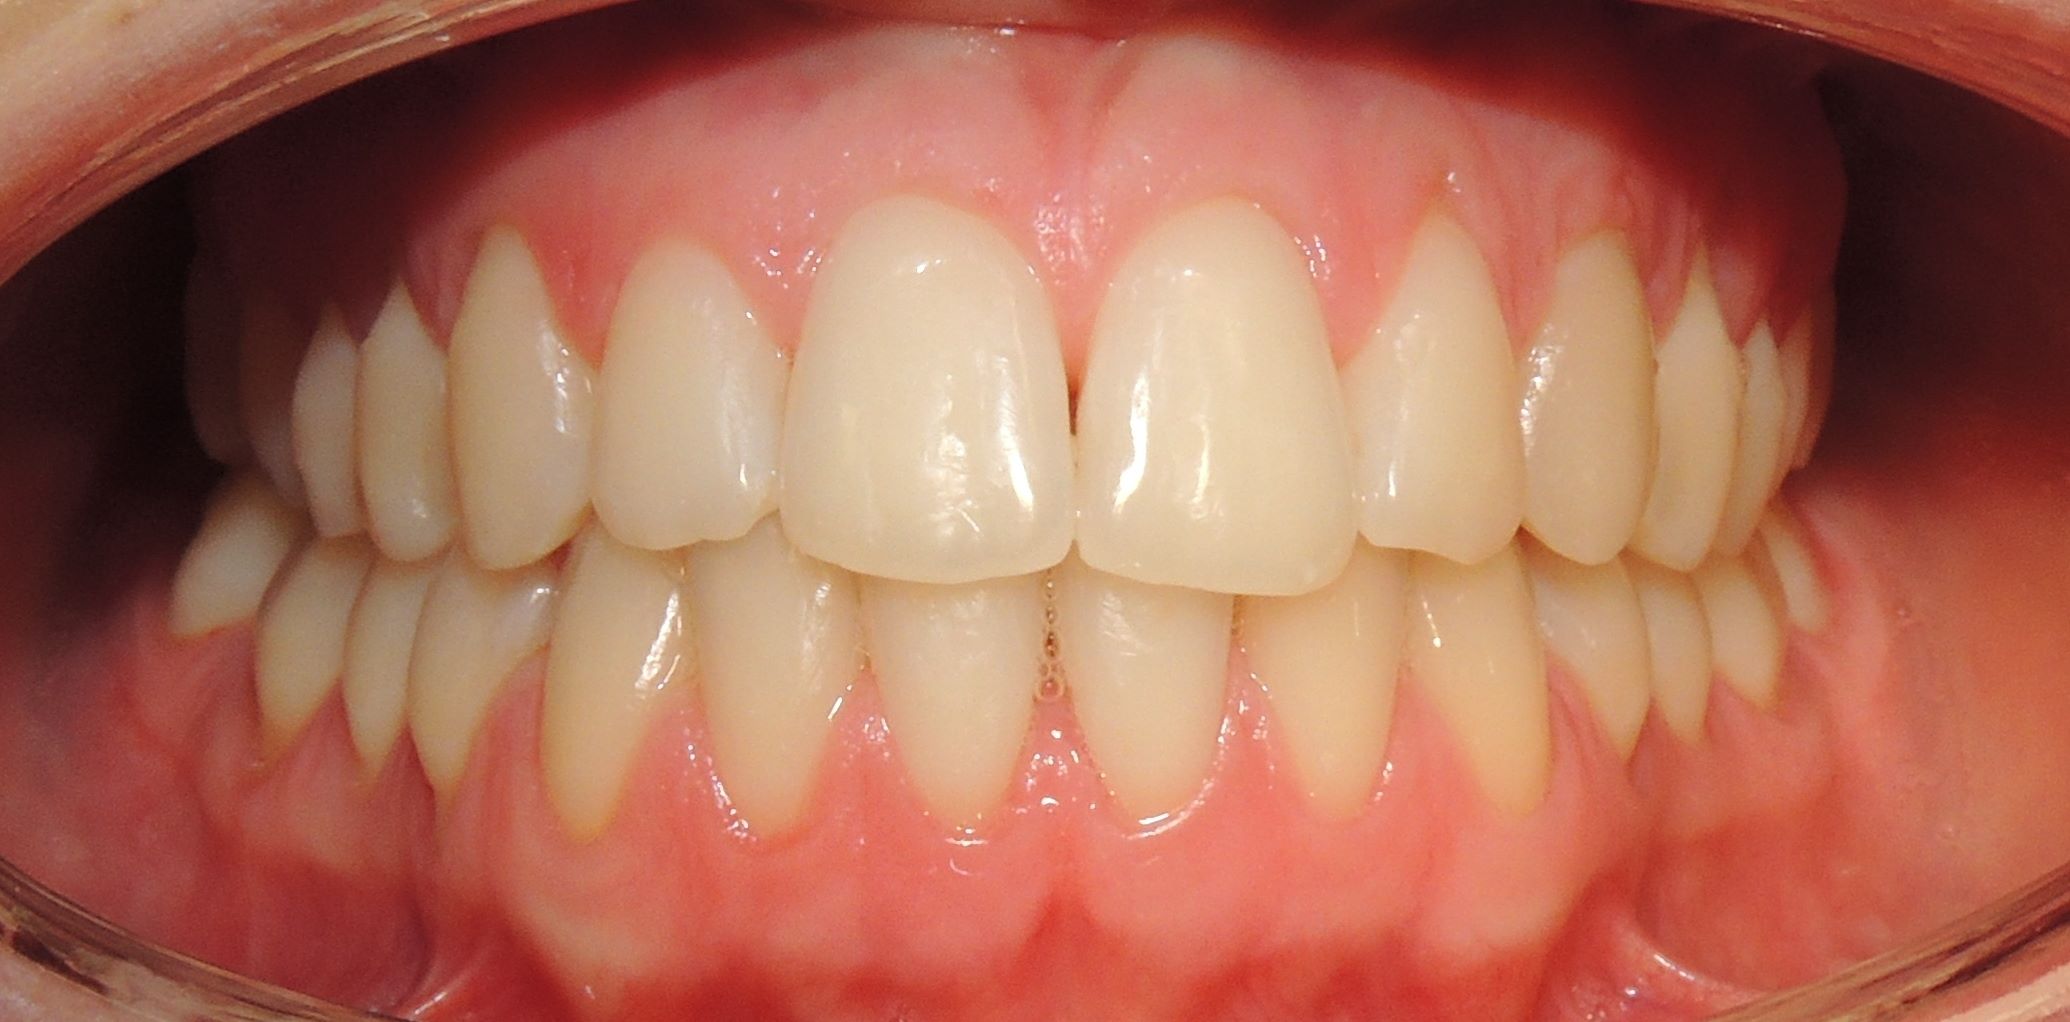

DRP + 2X2

17 dicembre 2016Disgiuntore Rapido del Palato e 2x2